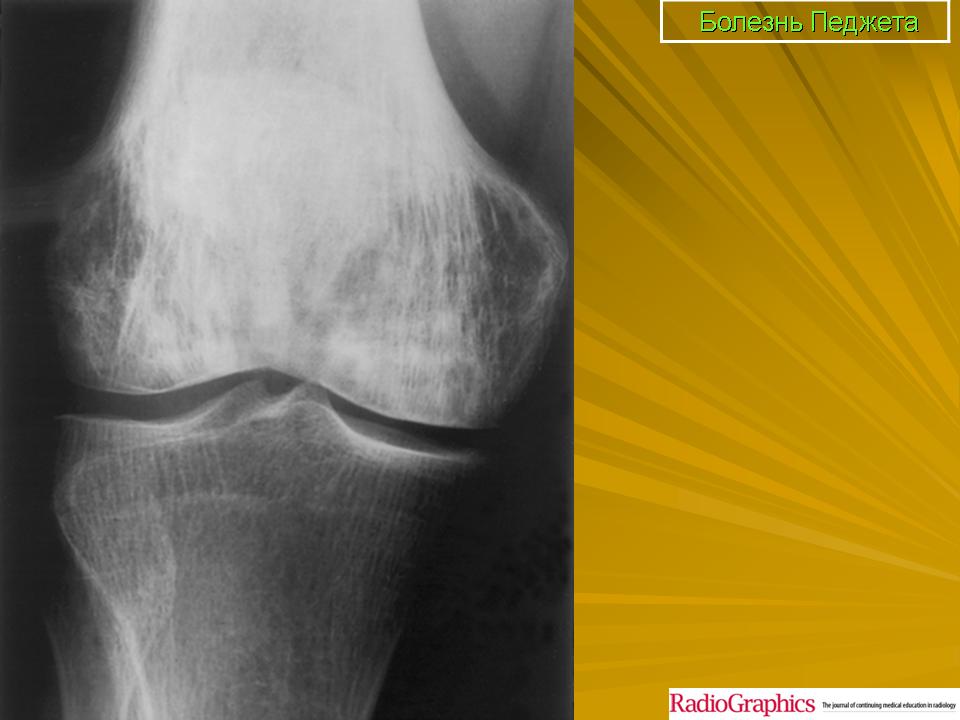

Литическая фаза.

Смешанная фаза.

Бластная фаза

Принято различать три фазы развития П. б.: очаговая интенсивная резорбция кости (остеолитическая, или деструктивная, фаза), смешанная фаза, когда наряду с рассасыванием кости идут процессы новообразования ее, и остеобластическая, или склеротическая, фаза с образованием типичных мозаичных структур.